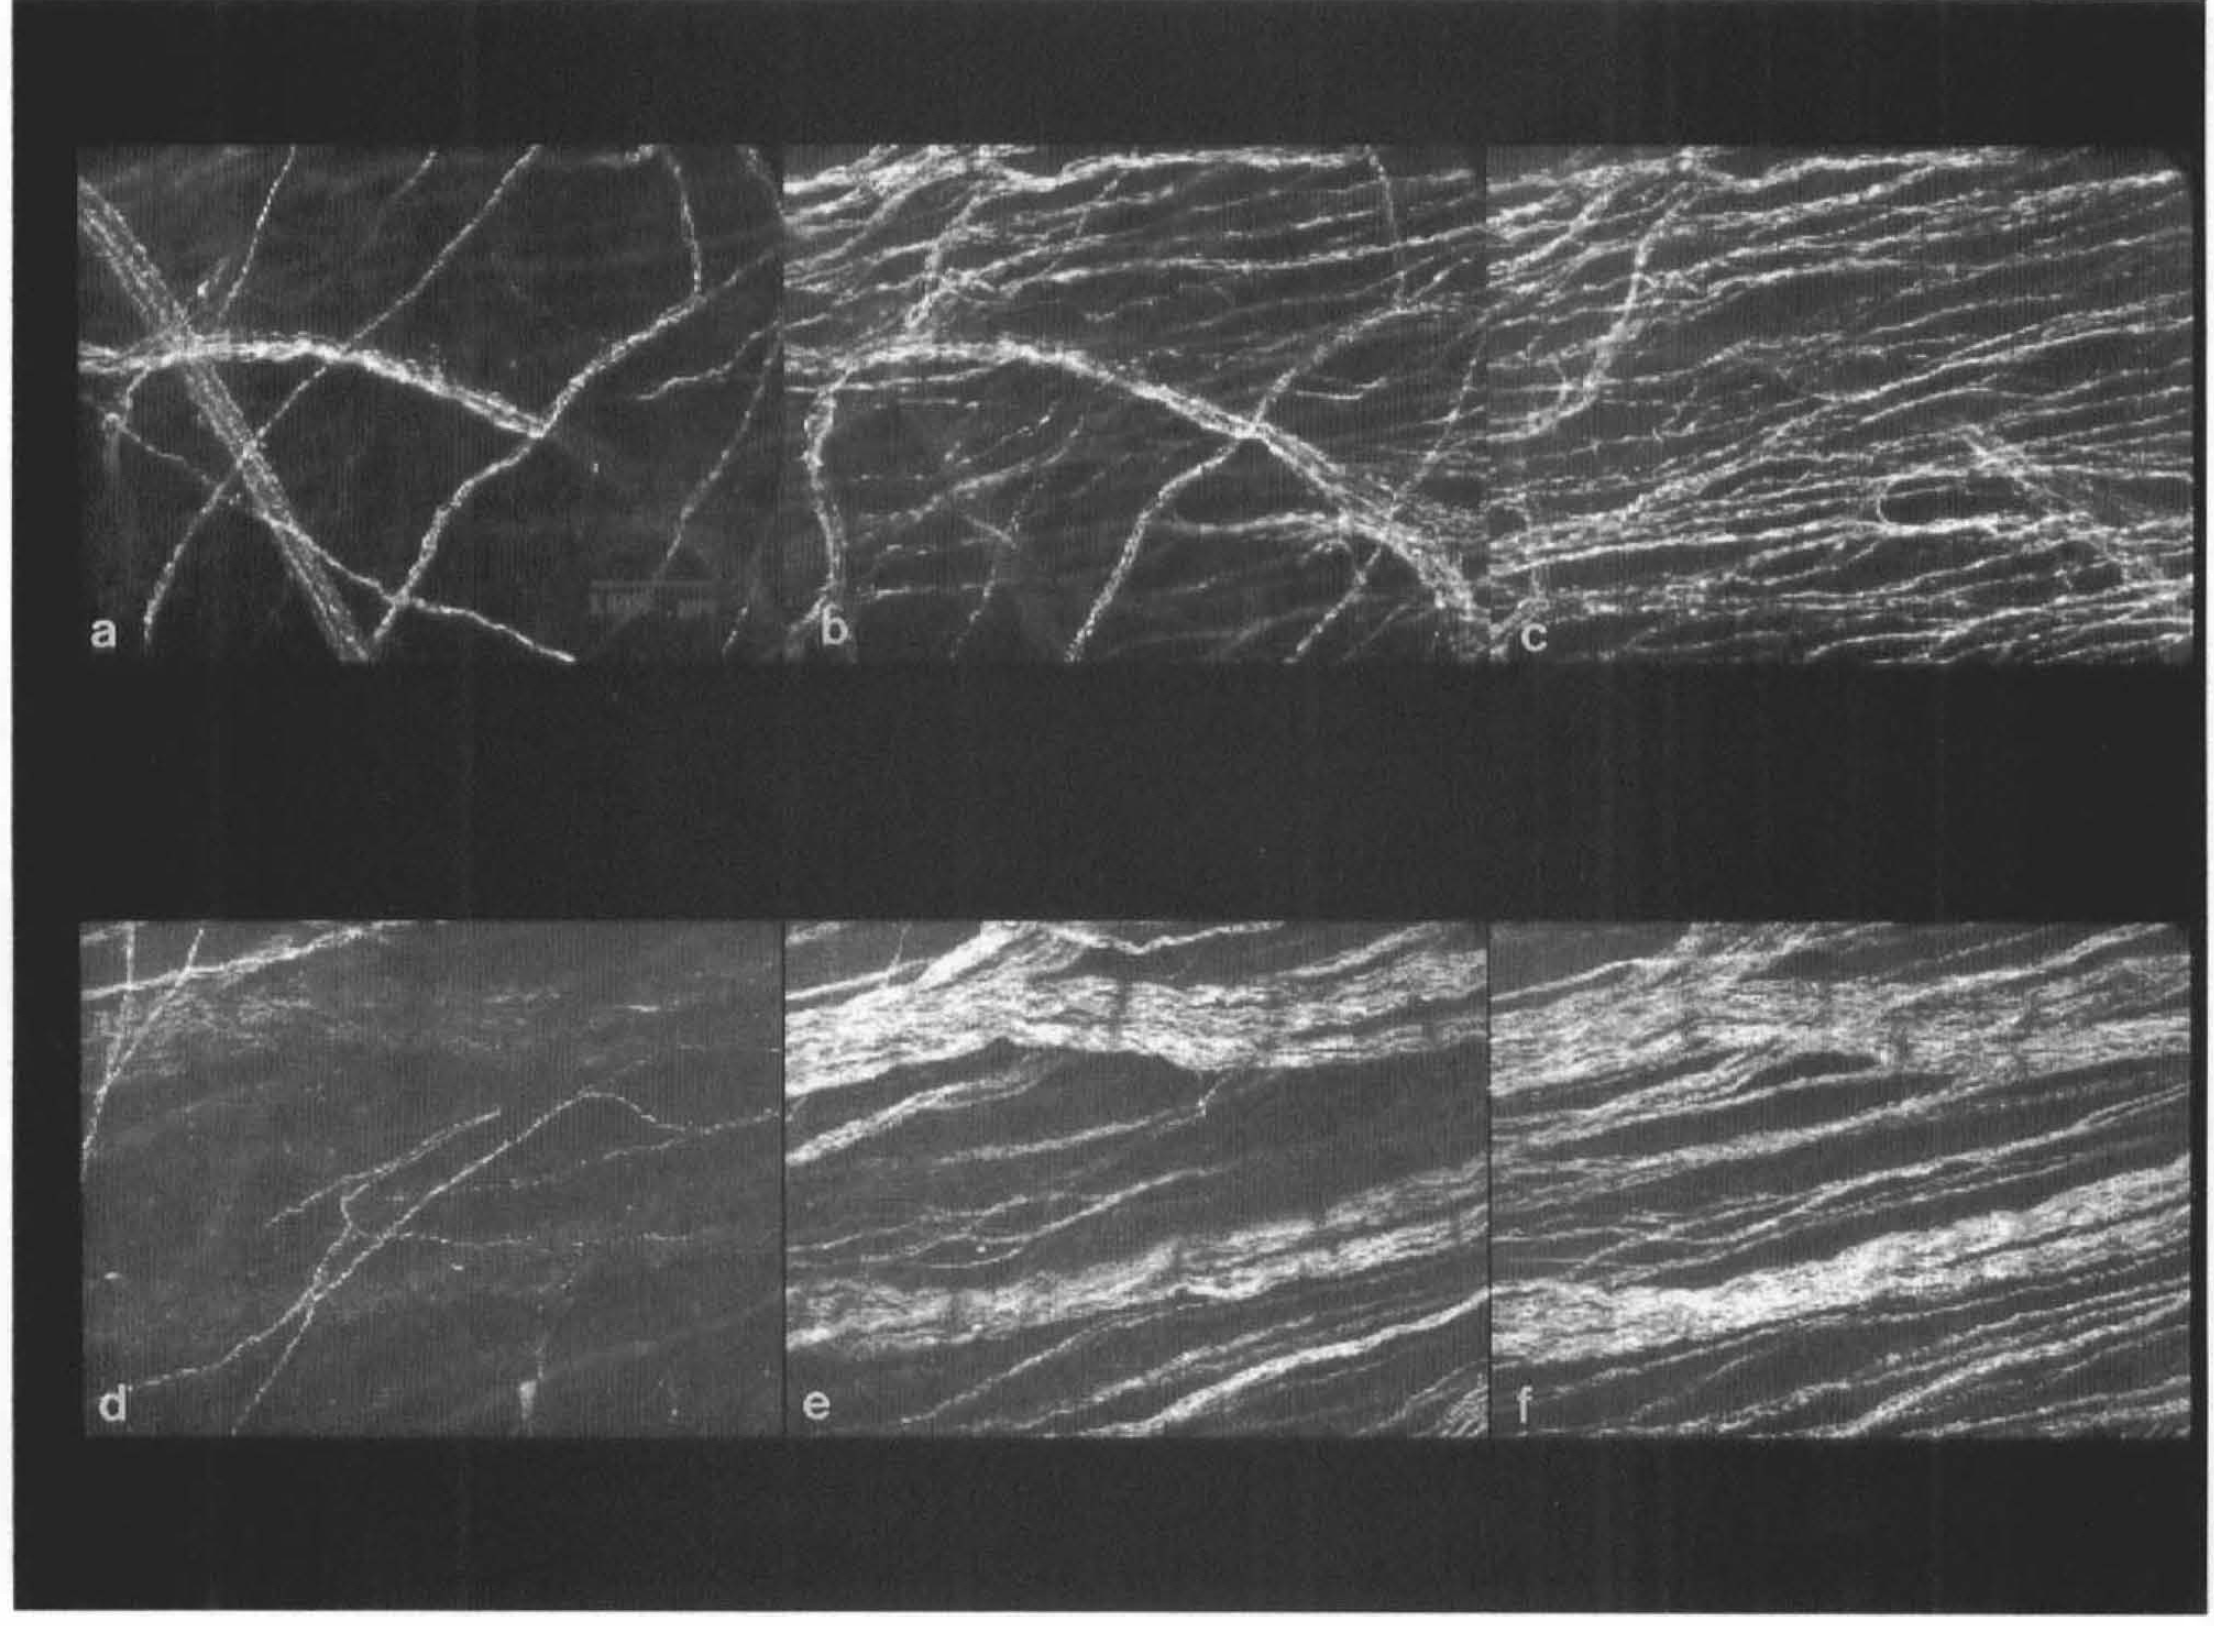

The method described for whole-mount preparations resulted in good staining quality in many cases, characterized by a well-defined, transversely oriented deep plexus. Not only deep plexuses, but also superficial plexuses were visible, depending on the degree of adventitial delamination. The superficial plexus formed a meshwork. In specimens that were used in the earlier experiments for establishing the staining procedure and that had not been delaminated, a three-layered plexus of nerves could be seen by focusing through the adventitia: (a) large longitudinally arranged nerve bundles, outside the adventitia; (b) a superficial plexus with large meshes within the adventitia; and (c) a deep, transversely oriented, plexus at the adventitial–medial border. Figure 2 shows some of the staining results of the middle-aged specimens. The transversely oriented nerves of the deep plexus were usually of a fine caliber and medium density. However, in contrast, the deep plexus of the PCom consisted of very thick, dense bundles of nerve fibers with varicosities (Fig. 2c). The anterior choroidal artery (ChA) contained not only a dense deep plexus, but also many longitudinally oriented, superficial nerve bundles (Fig. 2f).

Whole-mount preparations of perivascular nerves of several human cerebral arteries, stained for PGP 9.5. The deep plexuses are transversely oriented and located at the adventitial–medial border,

Confocal microscopy showed two principal layers of nerves within the adventitia of the PCom and MCA (Fig. 3). In some vessels, superficial nerve bundles were relatively sparse and connected via a few branches with a dense, deep terminal plexus.

Confocal videomicrographs of MCA (

Staining results of the fetal specimens are shown in Fig. 4. Two plexuses were clearly visible: an extremely regular meshwork-like superficial plexus and a transversely oriented deep plexus of fine fibers and of low density, containing few varicosities.

Whole-mount preparations of perivascular nerves of several human cerebral arteries from the fetal specimen, stained for protein gene product 9.5.